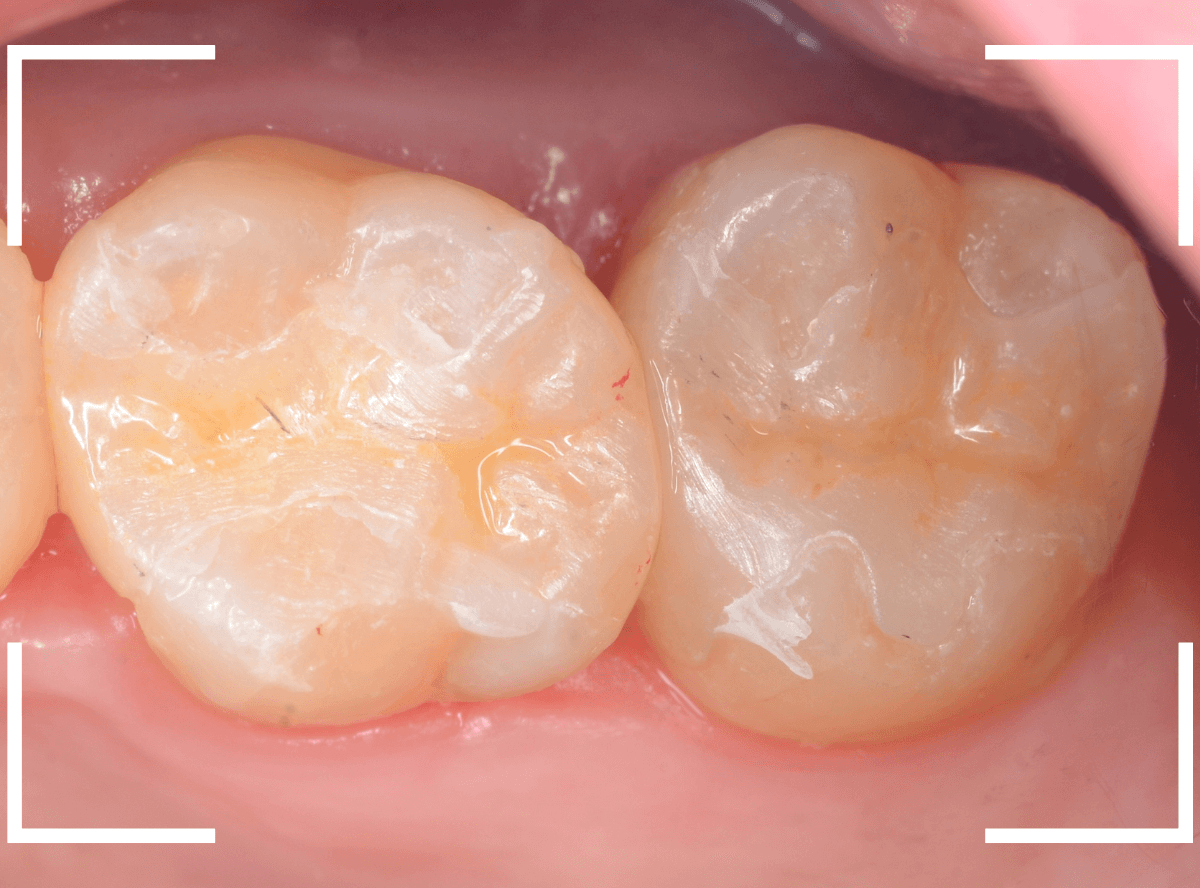

Case.29

舌のそばの虫歯とセラミック治療

模型上で精密に製作します。

治療後の状態です。

自然な仕上がりで、患者さんにもご満足いただけました。

| 治療回数 |

3回 |

| 治療期間 | 3週間 |

| 費用 | E-MAX・インレー (50,000円) ジルコニア・インレー (70,000円)x2 +保険治療費用(虫歯除去など) |

(2024年10月)